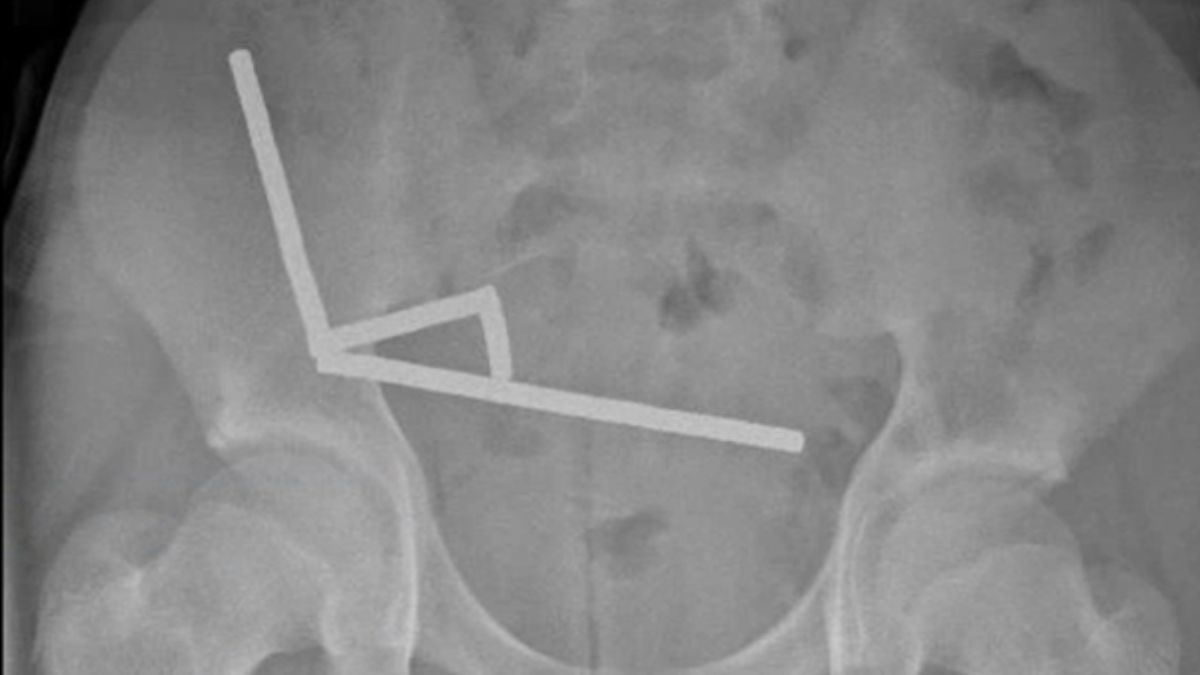

Using an X-ray, doctors imaged four linear chains in separate parts of the boy's bowel.

Once inside his abdomen, the small metal objects came together in a destructive way.

During surgery, the chains were found in separate sections of the small bowel and caecum. Squeezing together, they were causing several patches of tissue t